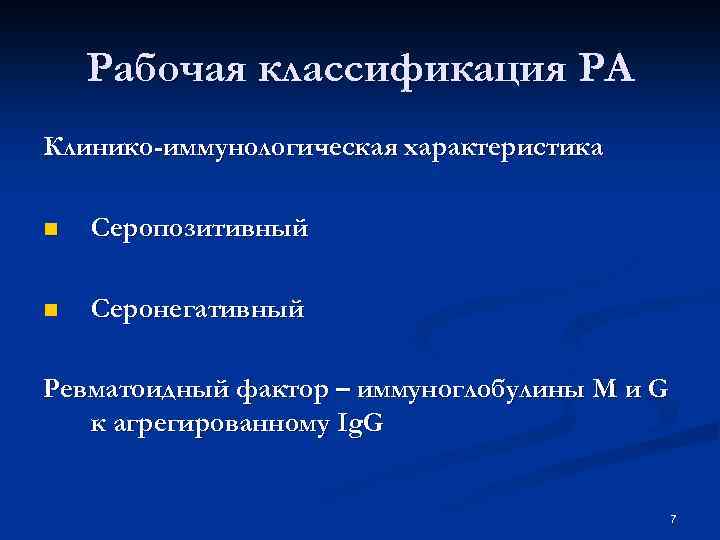

Рабочая классификация РА Клинико-иммунологическая характеристика n Серопозитивный n Серонегативный Ревматоидный фактор – иммуноглобулины M и G к агрегированному Ig. G 7

Рабочая классификация РА Клинико-иммунологическая характеристика n Серопозитивный n Серонегативный Ревматоидный фактор – иммуноглобулины M и G к агрегированному Ig. G 7